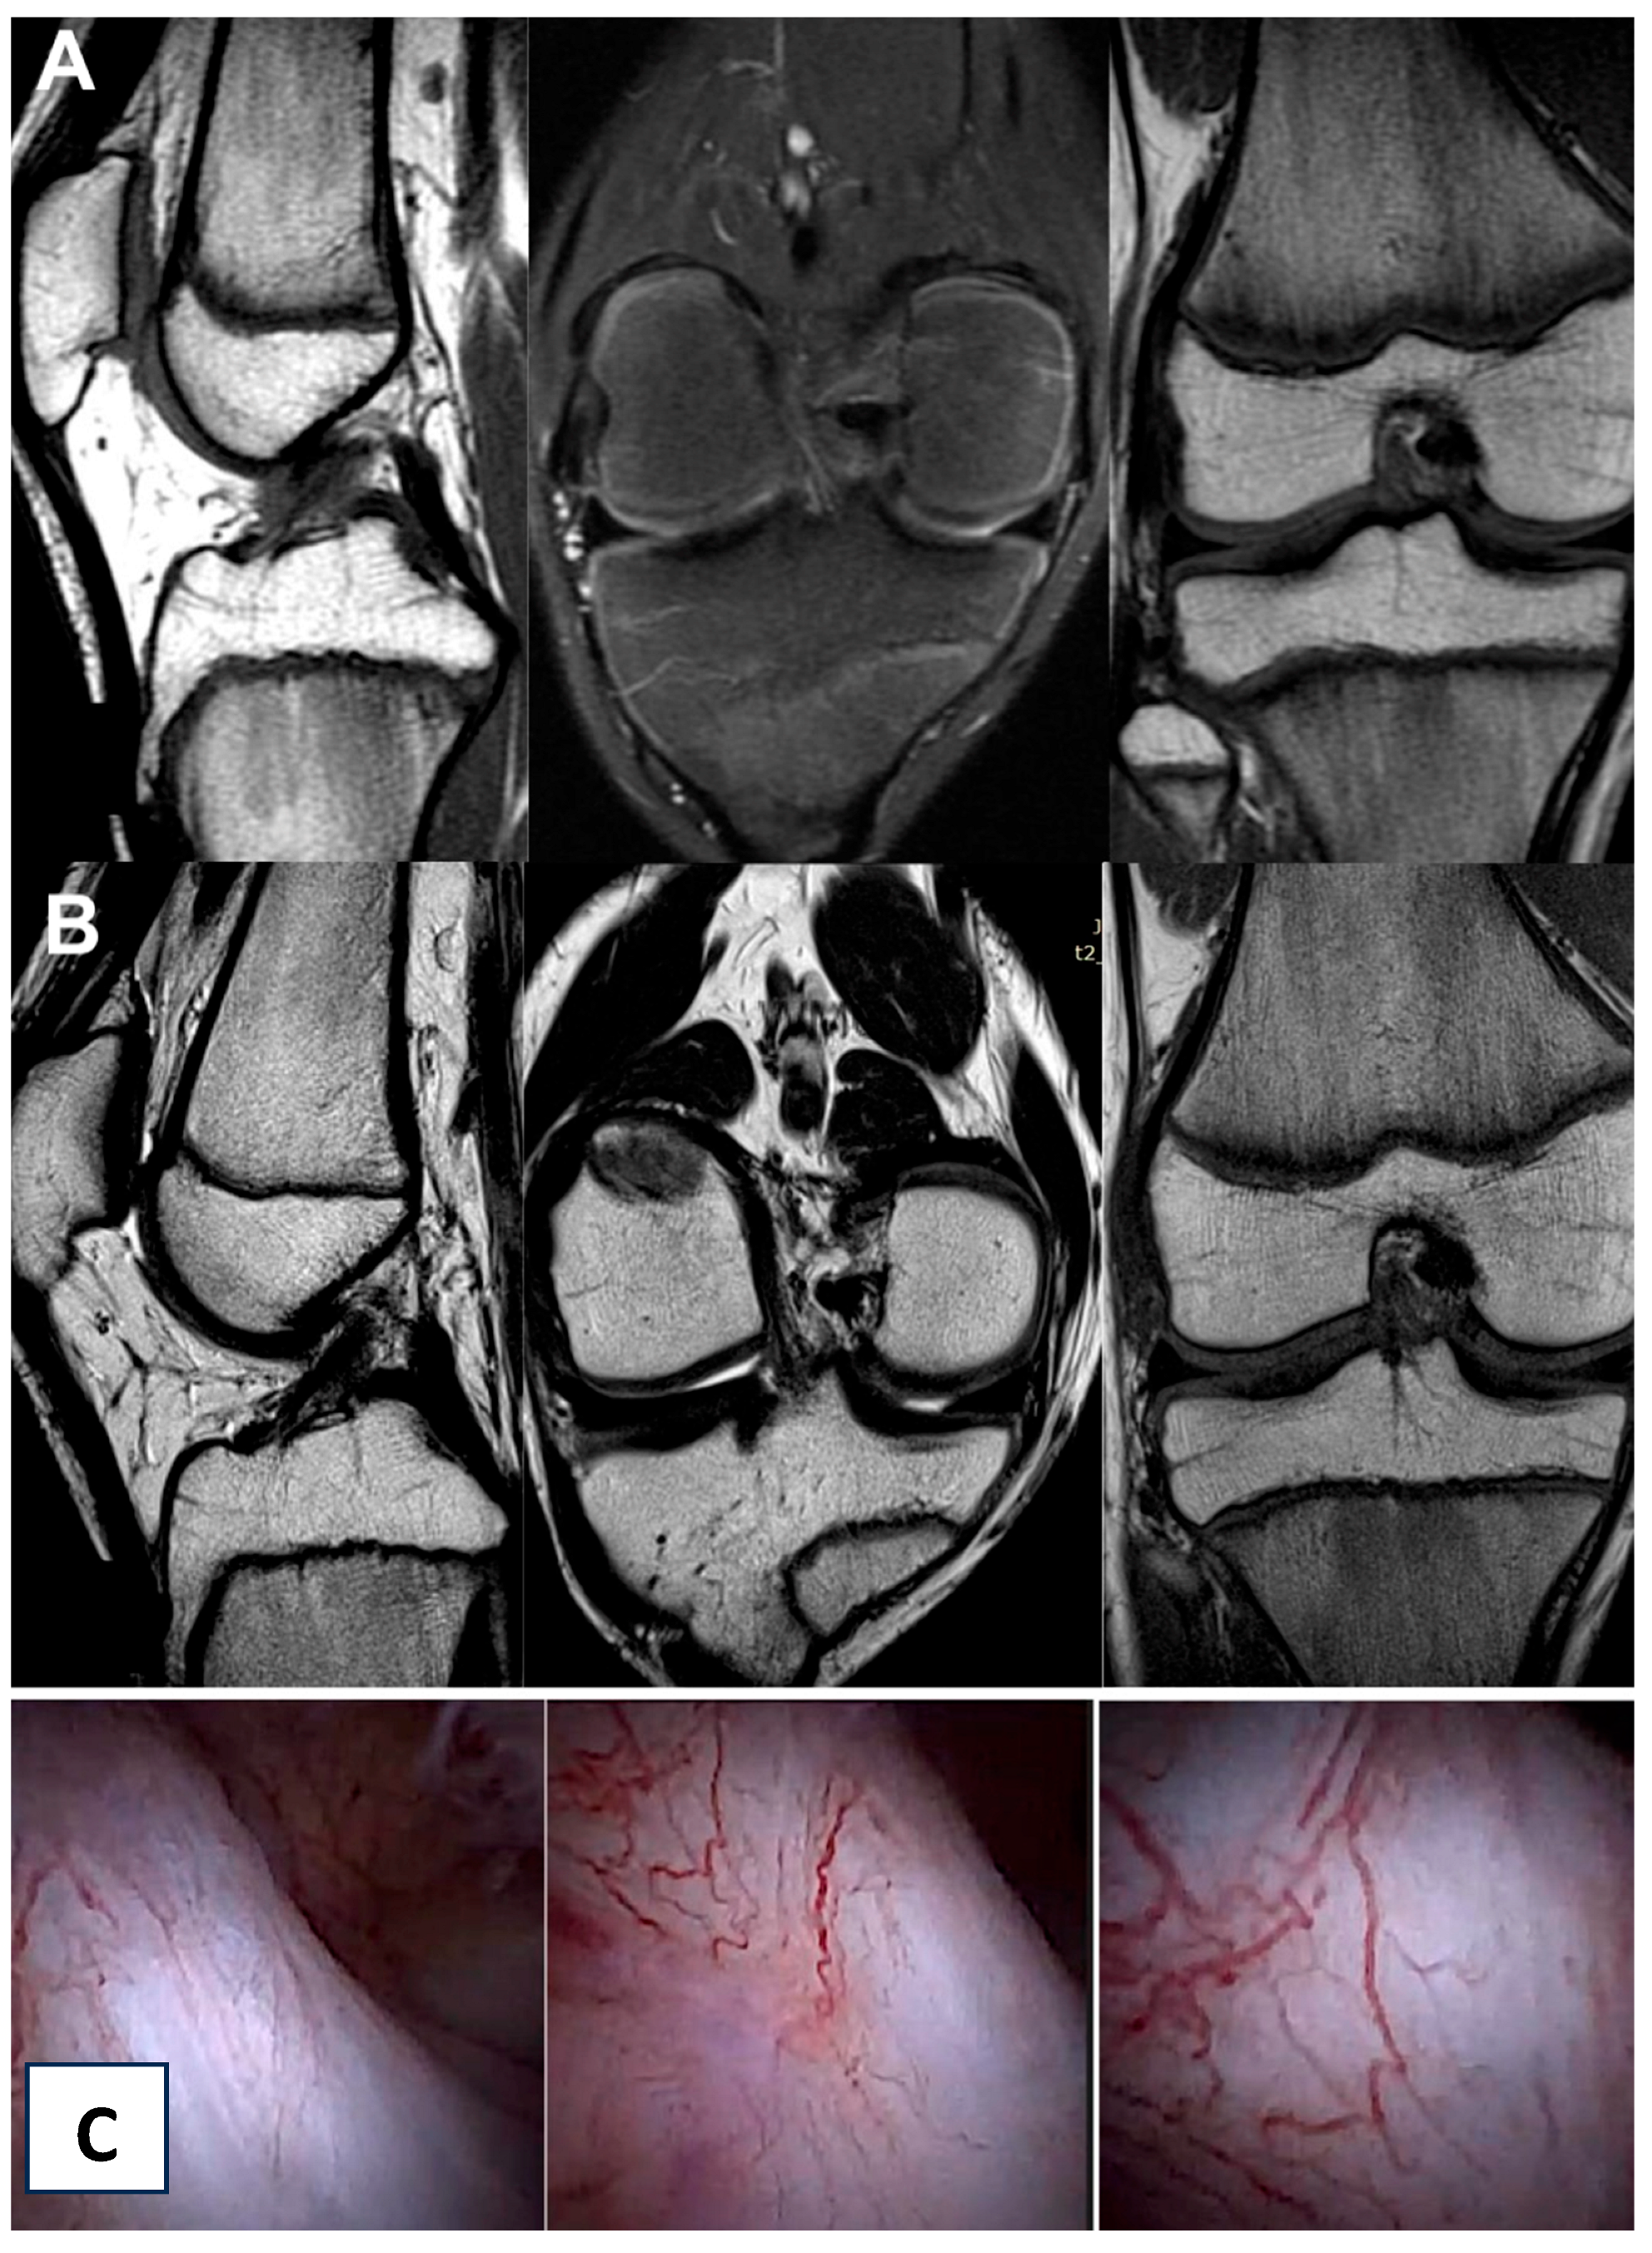

3.3. Imaging Analysis